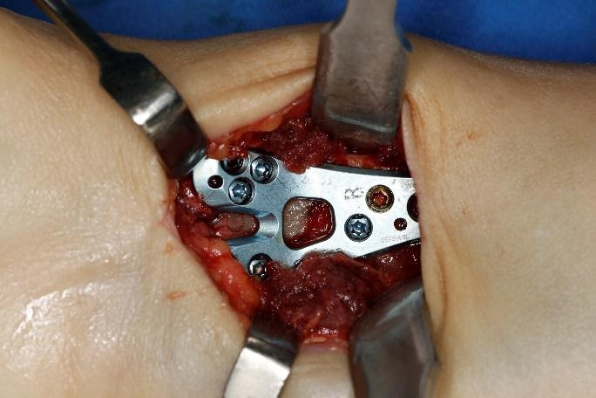

Konservatif tedavinin uygun olmadığı durumlarda cerrahi tespit önerilebilir. Distal radiusun sabitlenmesinde artık en yaygın yaklaşım, bileğin volar yönündendir. Bu, anatomik volar kilitleme plakasının kullanılmasını gerektirir. Birçok avantajı arasında daha az fark edilen bir cerrahi yara izi yer alır; kilitleme vidalı titanyum plaka daha iyi stabilite sağlar ve özellikle osteoporotik kemikleri olan hastalar için endikedir. Ulnar stiloid tabanda kırılmışsa kırığın onarılması tavsiye edilir.